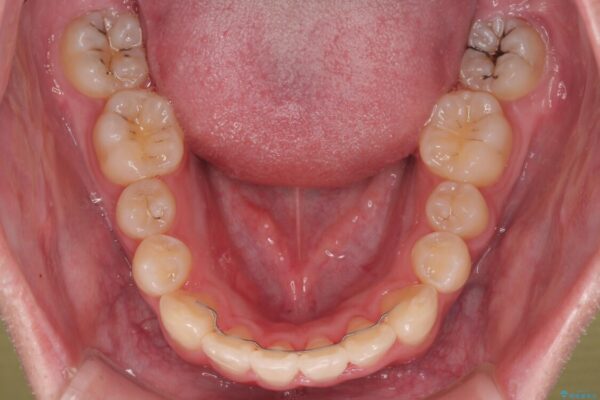

初診時の状態

・上下ともに歯がきれいに並びきらず、がたつきが見られました。

・上下の前歯の中心(正中)がずれています。

・特に上顎の幅が狭いため、下顎の歯列も内側に入り込み、歯が並ぶスペースが不足していました。

治療前

• 1年でここまで変わる!歯列のがたつきと正中のズレを改善した矯正治療(メタルブラケット×MARPE) 治療前画像